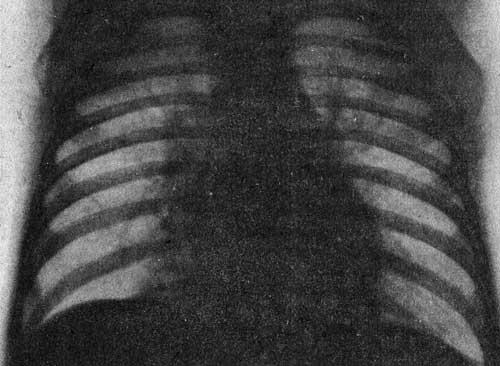

Аденовирус часто влияет на нижние отделы дыхательных путей, вызывая бронхиолит, круп или вирусную пневмонию, которая встречается реже, но может вызвать серьезные осложнения. Аденовирус также приводит к сухому, резкому кашлю, который иногда напоминает коклюш.